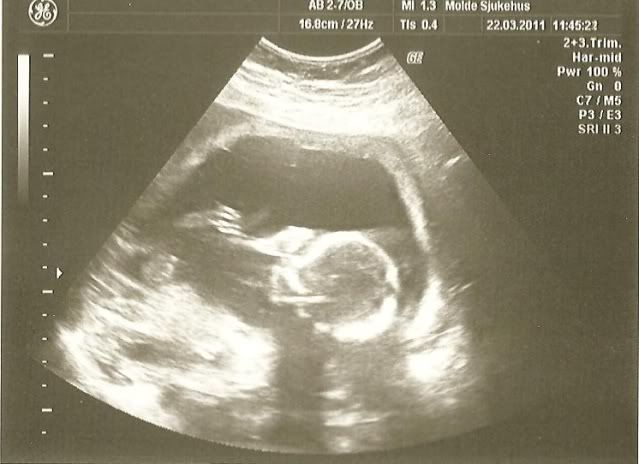

Her er et par bilder fra ultralyden for et par uker siden.